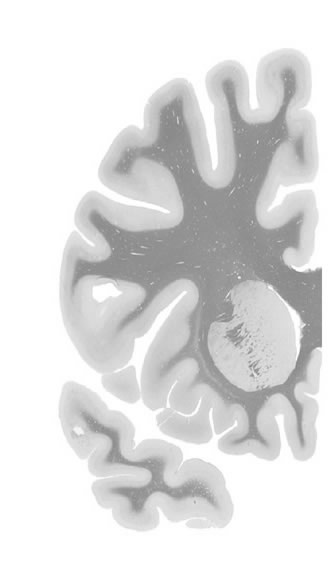

Frontal sections (Nissl) from the Atlas Brain: Gallery Slice Single

-17,9 mm

Slice ID: r2-0520

Plate NR: 10-11

Position: -17,9 mm